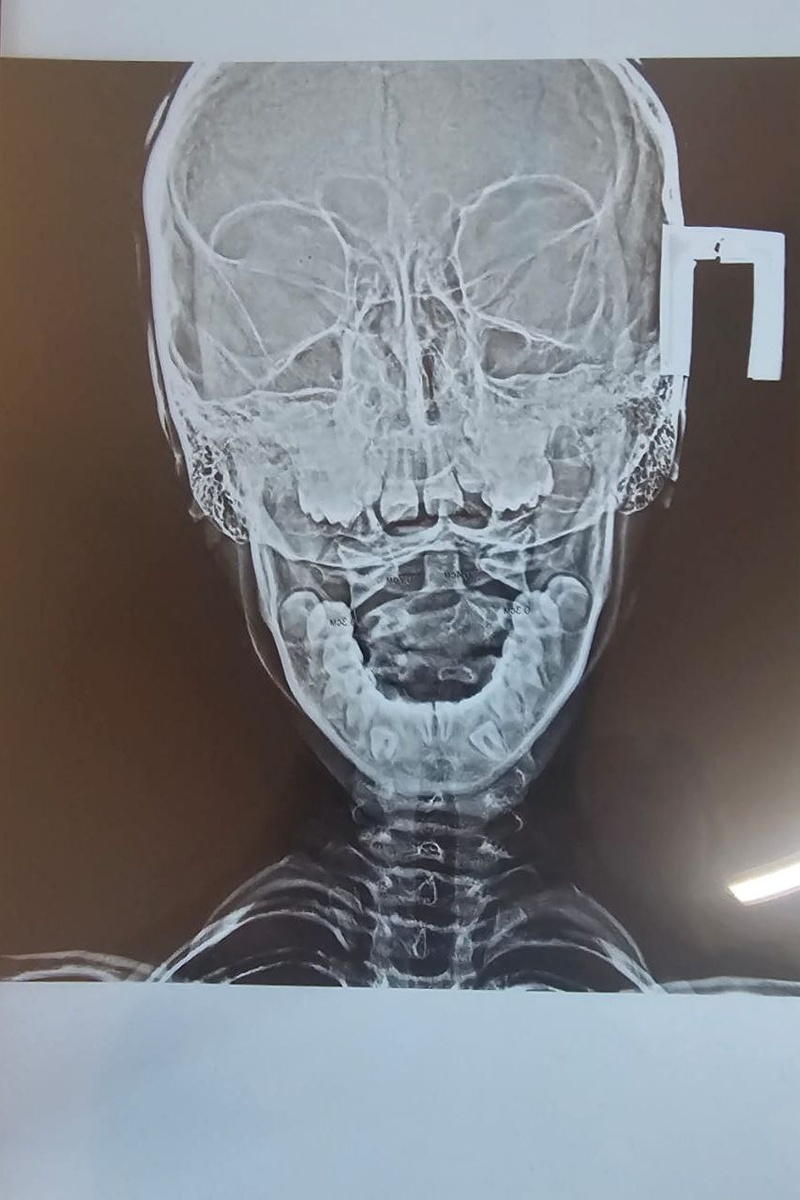

Ребёнка доставляют в травмпункт. Делают рентген, констатируют ротационный подвывих позвонка.

Мама с дочкой приехали на соревнования из другого города. На тренировке перед соревнованиями девочка совершает неудачно сложное техническое действие. Падение. Щелчок, голова набок, шея в неестественном положении.

Невозможно найти удобное положение для головы ни сидя, ни лёжа.

Голову приходится поддерживать руками. Иначе быстро появляется боль. Голова не поворачивается и не наклоняется совсем.

После сбора анализов, изучения результатов объективных методов исследования и собственного физикального обследования, я принимаю решение провести репозицию позвонка в его правильное физиологическое положение.

Ну, сказано - сделано. Манипуляция выполнена, и тут же функция восстановилась. Боли нет, голова поворачивается и наклоняется так, как нужно в рамках нормальных физиологических амплитуд.